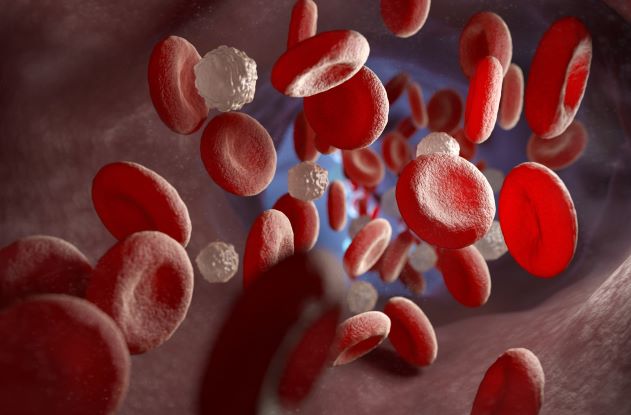

El mieloma múltiple (MM) es un tipo de cáncer hematológico (de la sangre) que afecta a las células plasmáticas de la médula ósea, lugar donde se fabrican los glóbulos rojos, blancos y plaquetas1.

Aunque no es tan frecuente como otro tipo de tumores como los de mama, pulmón o prósta, es el segundo cáncer de la sangre más común, después del linfoma No Hodgkin2, y el que más deteriora la calidad de vida por la enfermedad ósea y anemia que provoca3, así como otros problemas que fácilmente pueden confundirse con otros padecimientos retrasando con ello su diagnóstico y tratamiento oportunos4.

Expuso que las manifestaciones clínicas del mieloma múltiple también incluyen anemia, infecciones, sangrados y fatiga[xx], y son tan raras que pasan desapercibidas retrasando hasta por dos años el diagnóstico4.